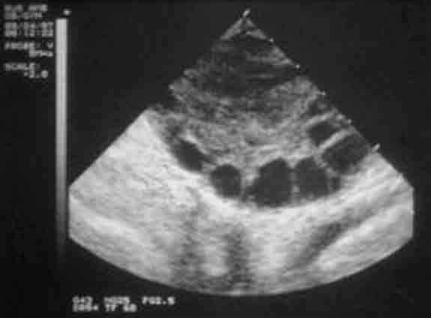

成熟卵泡的B超表現(xiàn):

1、卵泡呈圓形或橢圓形,直徑達(dá)15-30mm(21.2+-0.53mm),卵泡內(nèi)呈無回聲區(qū),清亮純凈,邊界清晰,壁菲薄。

2、20%成熟卵泡在排卵前一天,可見卵丘圖像,在卵泡內(nèi)近壁處呈短強(qiáng)回聲。